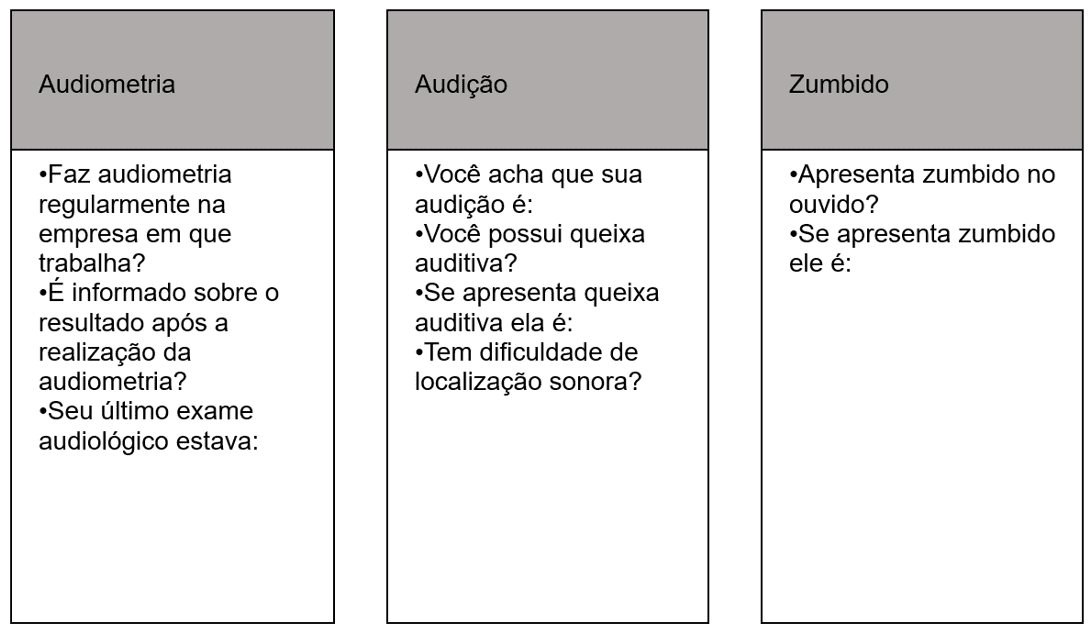

Percepção auditiva de trabalhadores petroquímicos

INTRODUÇÃO: Os trabalhadores que atuam em indústrias petroquímicas estão expostos a altos níveis de pressão sonora e também a produtos